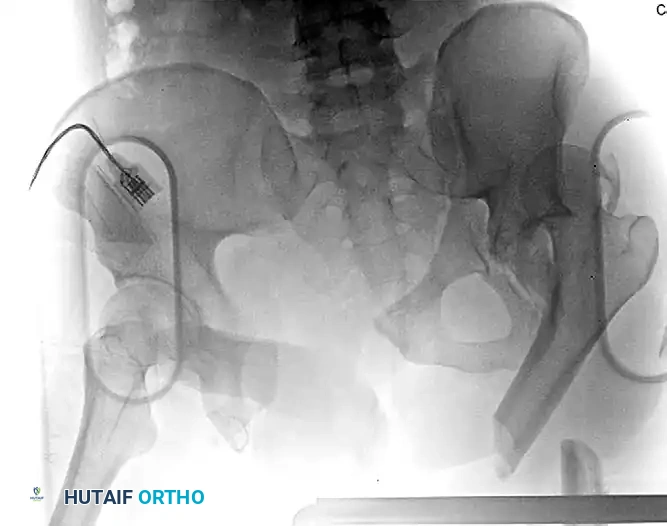

Figure 54-93 A: Polytraumatized patient with a left femoral diaphyseal fracture and an associated femoroacetabular dislocation. Note the concomitant complex pelvic ring and left-sided acetabular injury. The proximal femoral fragment is tethered in adduction, a hallmark radiographic sign of this combined injury.